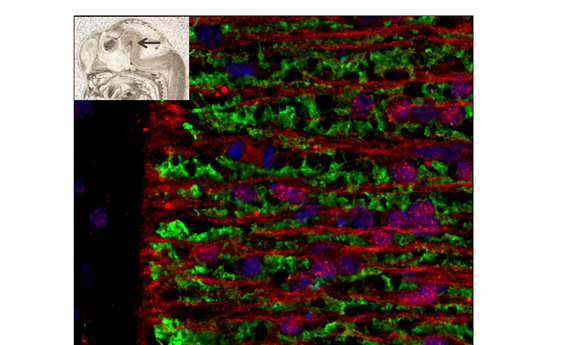

La falta de una única proteína acelera el envejecimiento muscular en ratones